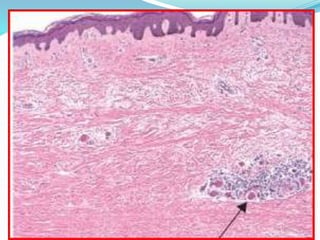

Morphology - Skin

 Diffuse, sclerotic atrophy of the skin

 Edema and perivascular infiltrates containing CD4+ T

cells

 Capillaries and small arteries show thickening of the

basal lamina, endothelial cell damage, and partial

occlusion

 Increase of compact collagen in the dermis, with

thinning of the epidermis, loss of rete pegs, atrophy of

the dermal appendages, and hyaline thickening of the

vessels.

• 46.

Morphology - Skin Diffuse, sclerotic atrophy of the skin  Edema and perivascular infiltrates containing CD4+ T cells  Capillaries and small arteries show thickening of the basal lamina, endothelial cell damage, and partial occlusion  Increase of compact collagen in the dermis, with thinning of the epidermis, loss of rete pegs, atrophy of the dermal appendages, and hyaline thickening of the vessels.